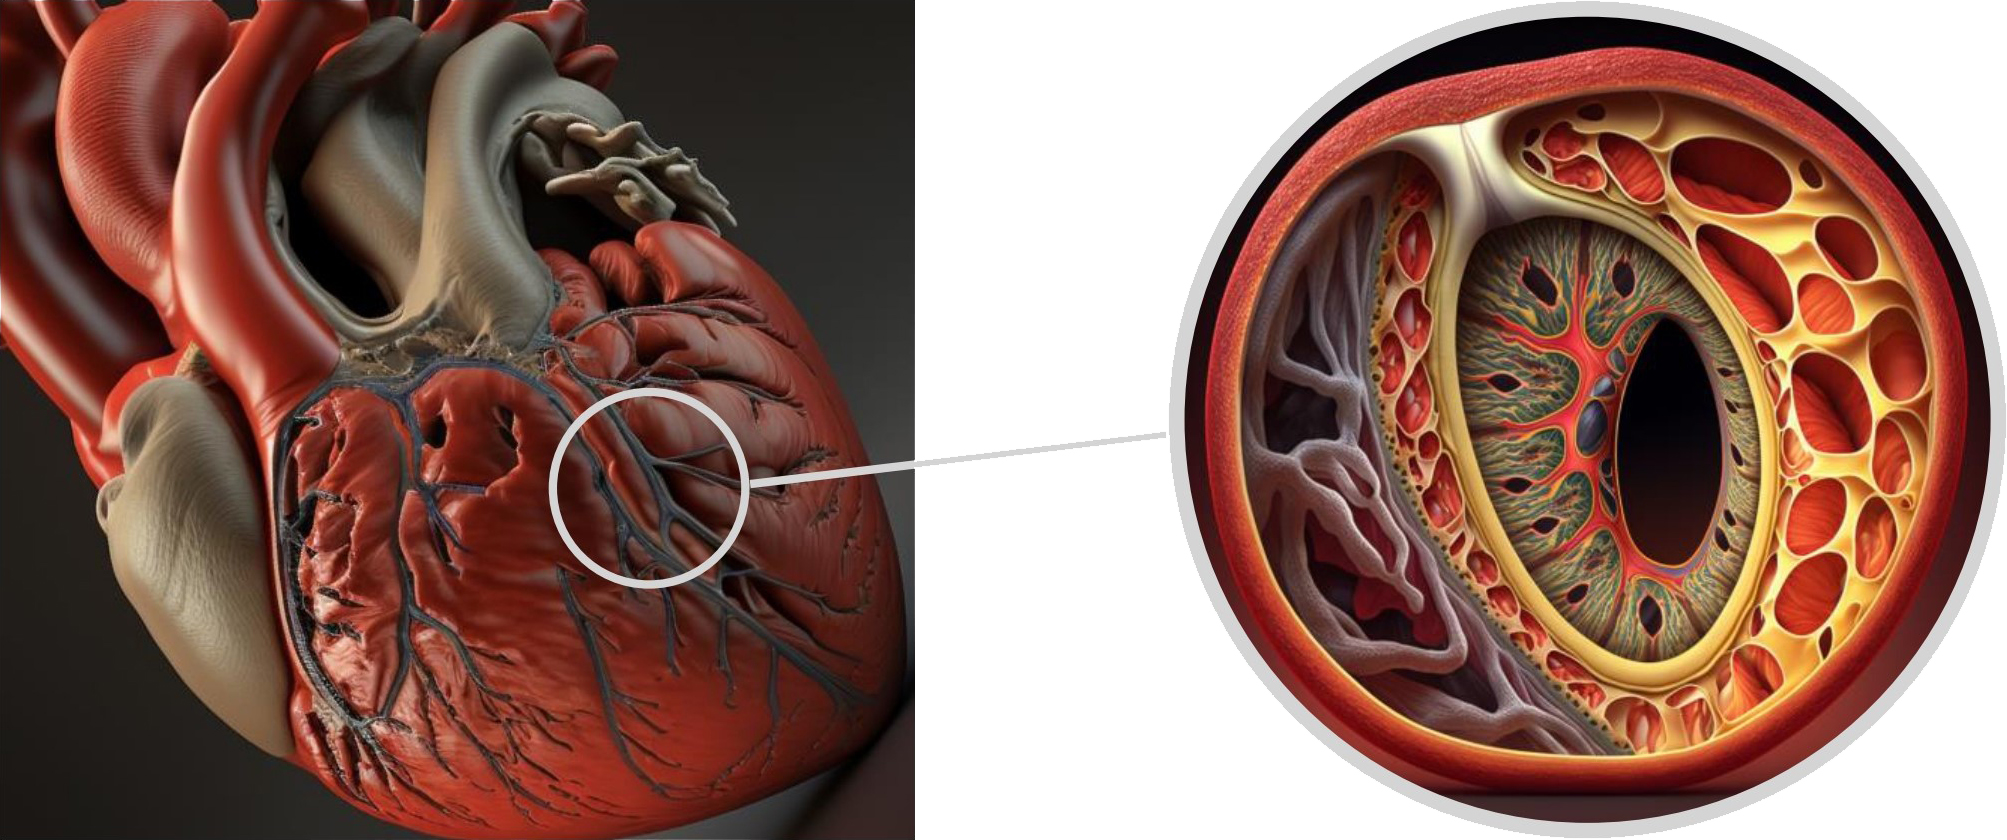

The arterial wall is composed of three distinct layers. The innermost layer, known as the tunica intima, consists mainly of endothelial cells and connective tissue. The middle layer, called the tunica media, is comprised of smooth muscle cells, while the outer layer, the tunica adventitia, is made up of collagen and elastic fibers and includes the vasa vasorum [5]. Coronary dissection occurs when an intramural hematoma forms, leading to the separation of the tunica intima from the outer layers and creating a false lumen that protrudes into the real lumen, ultimately reducing blood flow (Fig. 9).

Fig. 9.

Fig. 9.Tridimensional representation of LAD coronary artery dissection. LAD, left anterior descending.